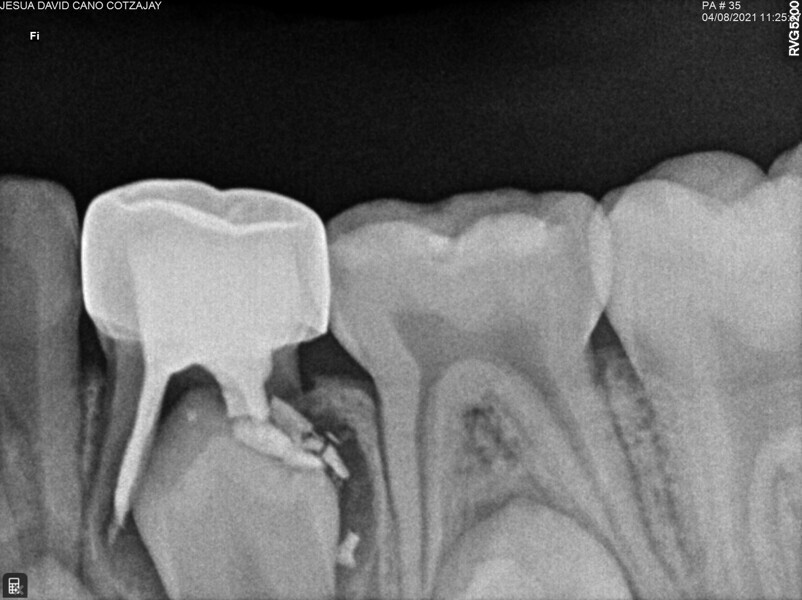

Ce patient âgé de 5 ans et 8 mois présentait des caries interproximales profondes sur la face distale d’une première molaire temporaire supérieure gauche, et un trajet fistuleux en vestibulaire. Le patient était asymptomatique et sans antécédents de douleur. Une nécrose pulpaire associée à une parodontite suppurée périapicale a été diagnostiquée. Trois canaux ont été localisés et préparés pour l’obturation. La préparation a montré une extrusion apicale excessive de ciment à l’oxyde de zinc eugénol (ZOE). Quinze jours plus tard, le patient était asymptomatique et le trajet fistuleux s’était résorbé. Il a donc été décidé de restaurer la dent avec une couronne en acier inoxydable. Le suivi réalisé à 30 mois a montré une cicatrisation périapicale de la zone apicale mésiale où siégeait la radioclarté observée précédemment, ainsi que l’absence de tout signe ou symptôme pathologique et de douleur.

Cas 5 (Figs. 19 à 23)